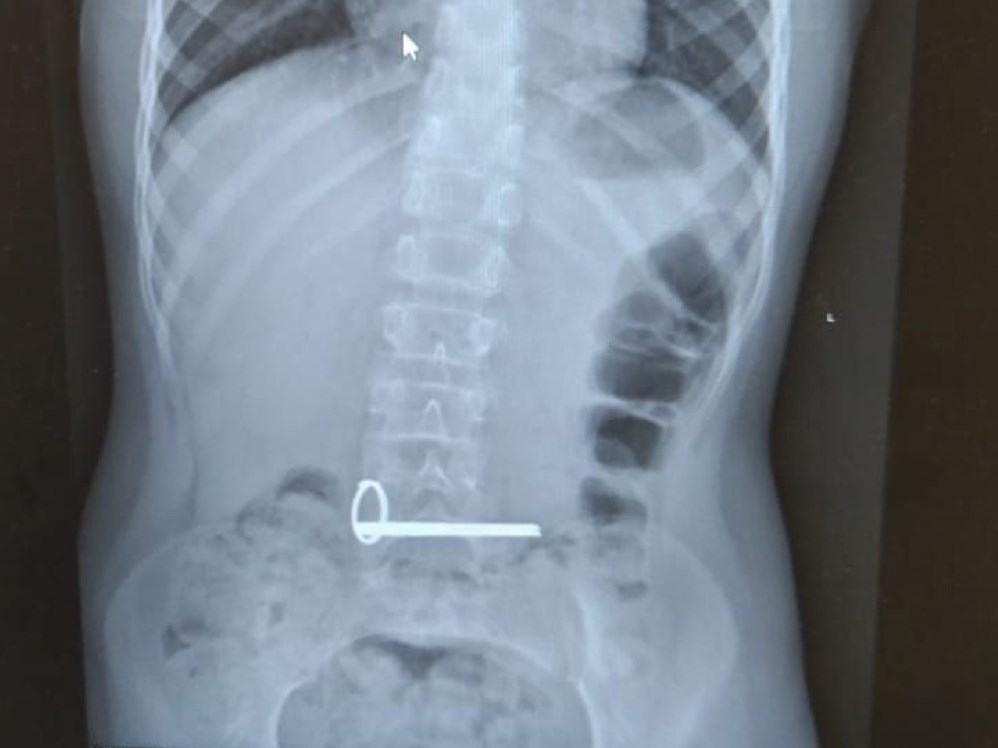

В отделение экстренной помощи областной детской больницы ребенка с инородным телом в желудке доставили ночью. Снимок показал наличие в ЖКТ школьника связки ключей.

фото: Оренбургская областная детская клиническая больница